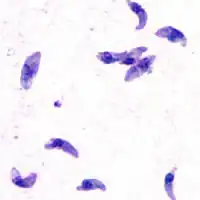

Tacozoítos de T. gondii